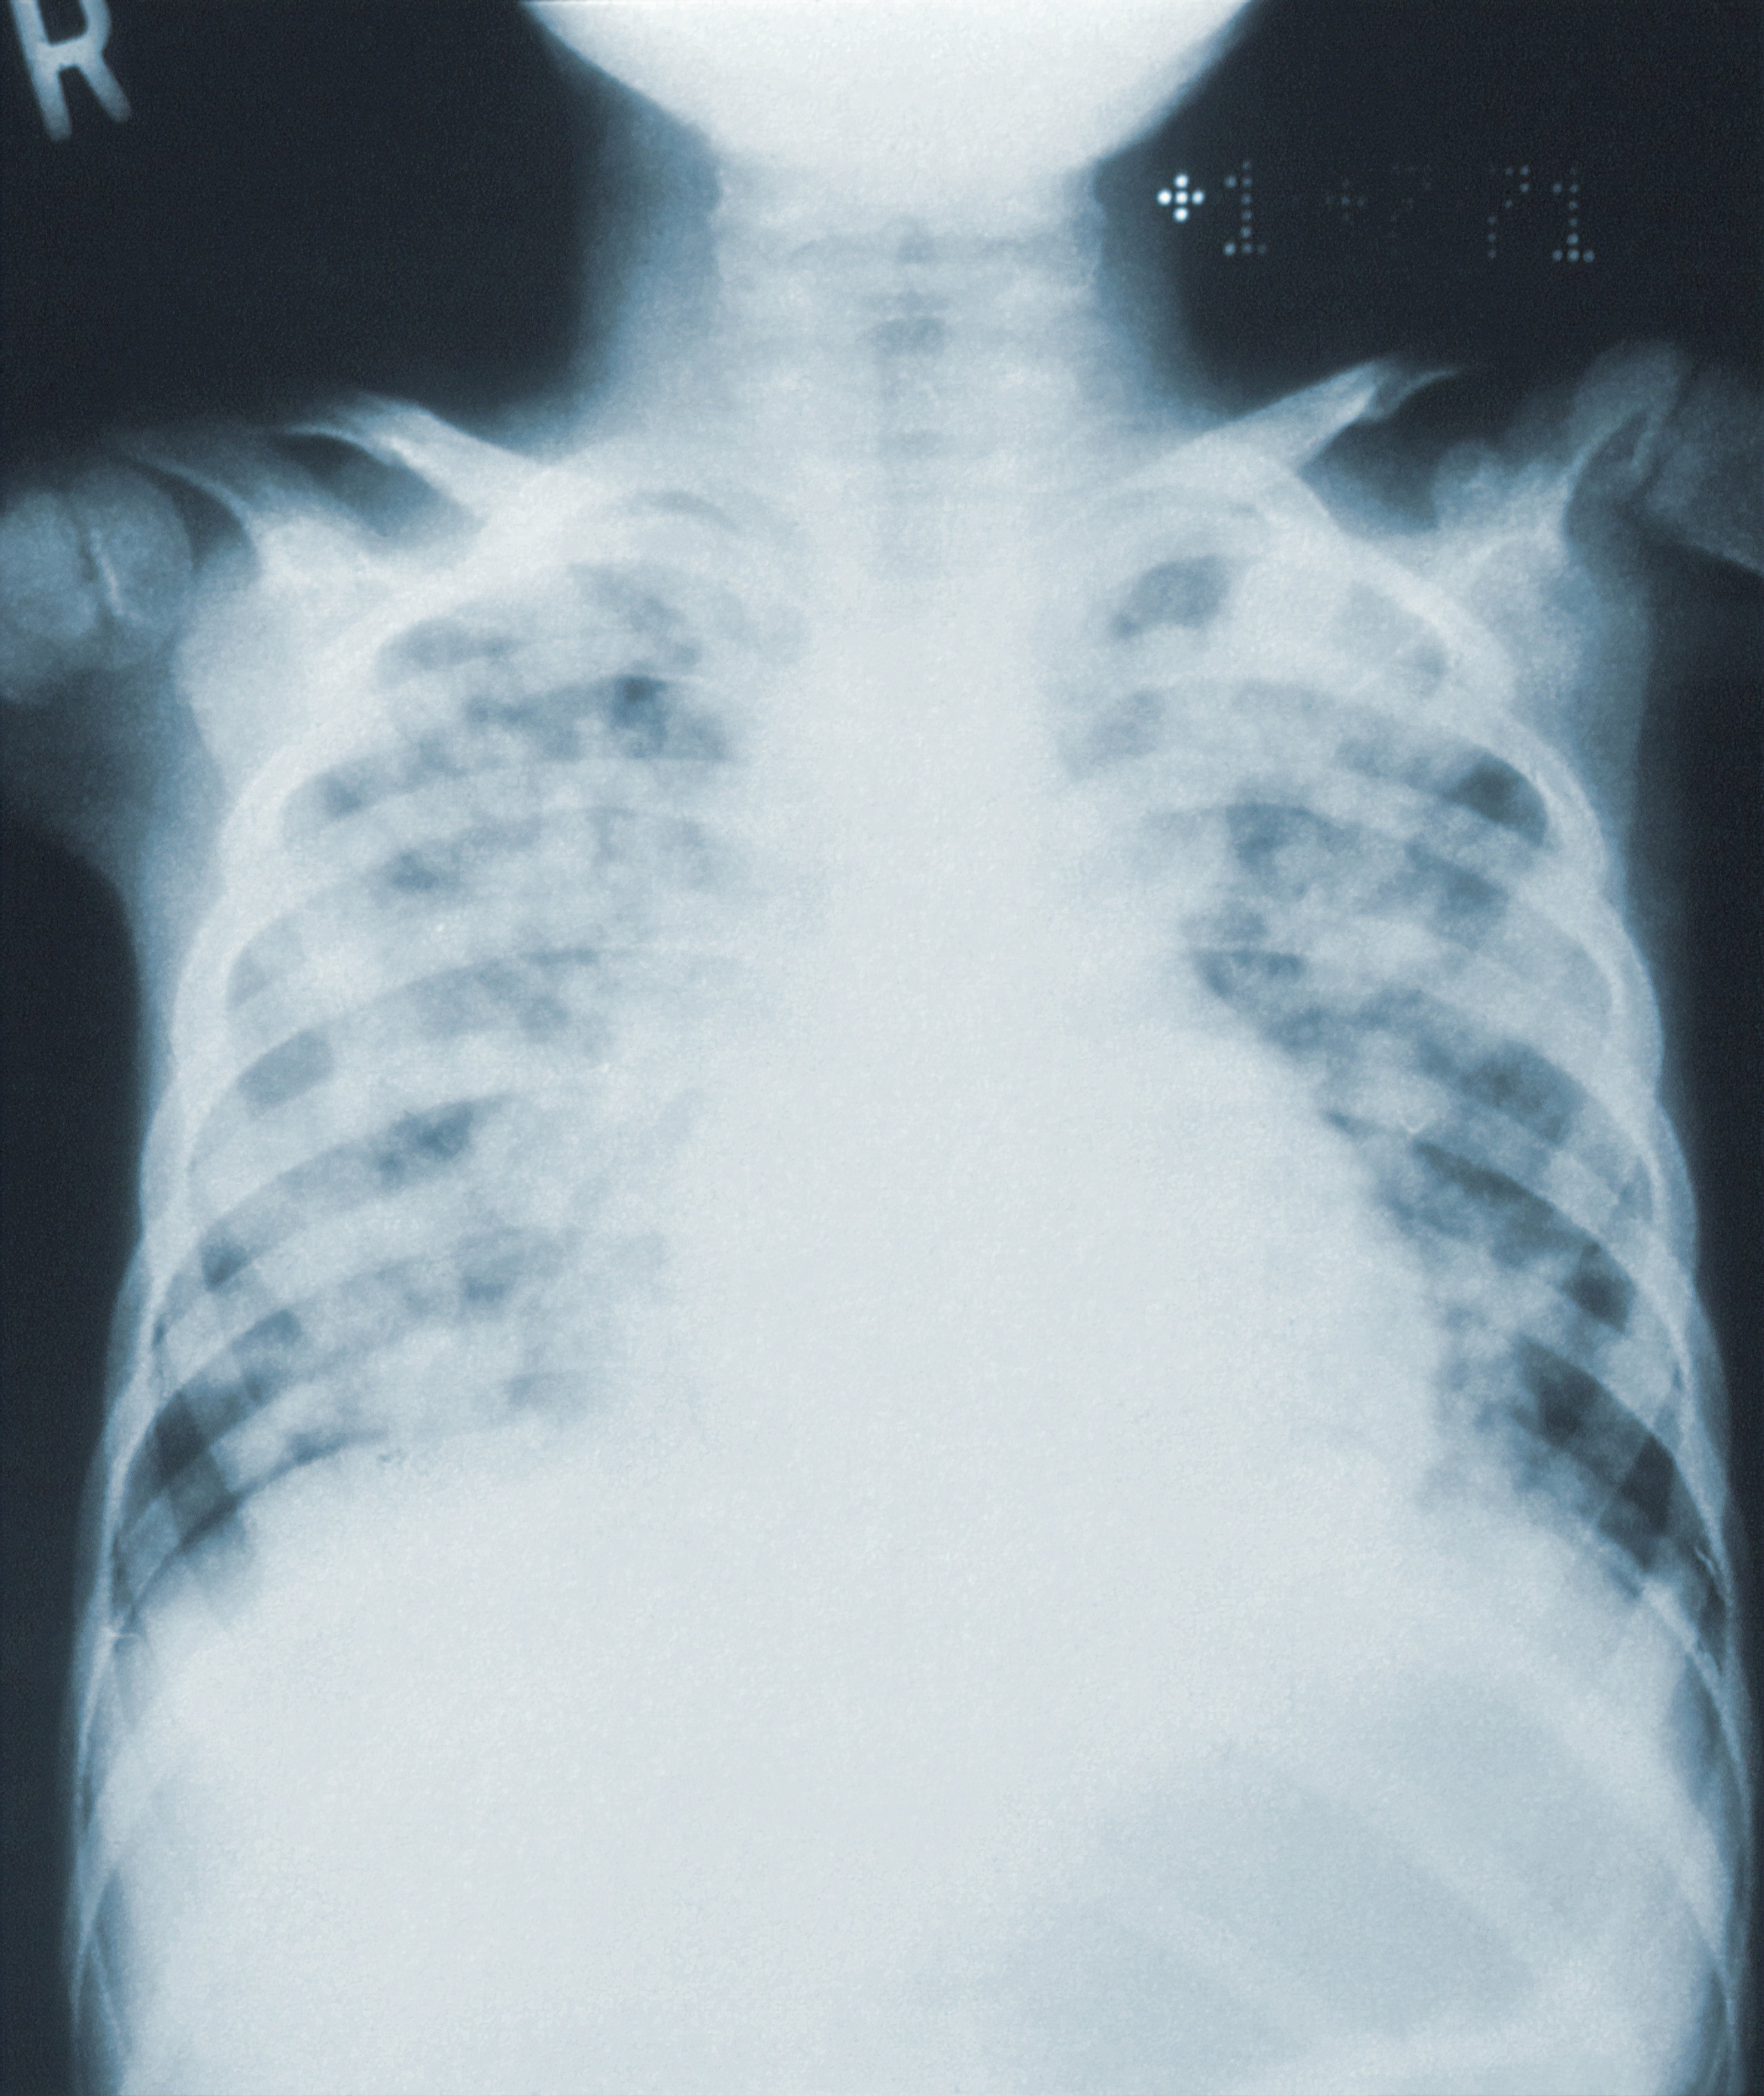

La neumonía “pulmón blanco” o neumonía por Micoplasma (Mycoplasma pneumnoniae) es una neumonía atípica que se relaciona con bacterias, que ocasionaría que las radiografías pulmonares capten imágenes blancas.